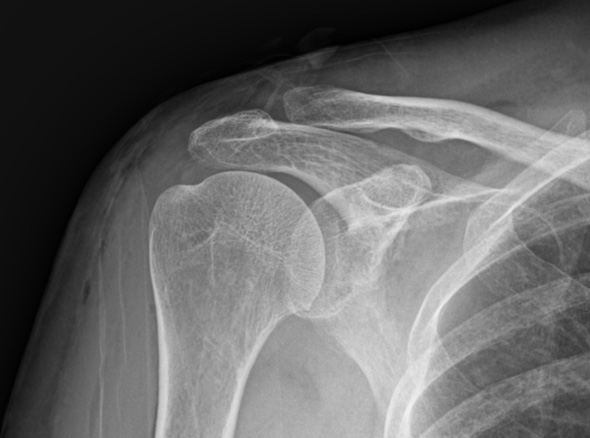

관절 내시경을 통한

석회제거술

내시경을 통하여 석회를 직접 보며,

힘줄 손상을 최소화시켜 석회 및 염증을 제거합니다.

수차례 충격파 치료 등에도 호전되지 않는 경우

주사 흡인술이 가능하지 않은 경우(오래되거나 딱딱한 석회)

1-2Cm 이상의 큰 석회

운동 범위의 감소가 매우 큰 경우

힘줄 파열이 동반되어 있는 경우